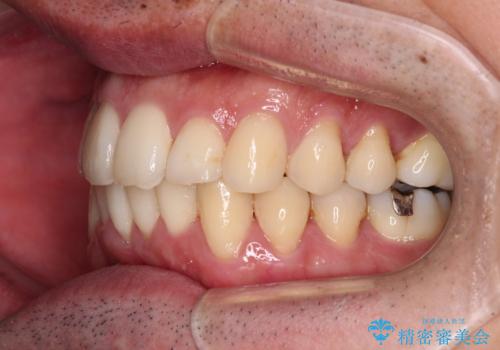

最終的にはゴムかけなどを活用して改善することができましたが、4年近い治療期間を要することとなりました。

下顎骨が顕著な左右差を持って成長したため、右側にずれている状態でした。

この方は元々骨格的な偏位が大きかったためか、治療中に下顎骨が上顎骨よりも右外側に誘導されて、右側の奥歯が全く咬合しない状態が続いてしまいました。